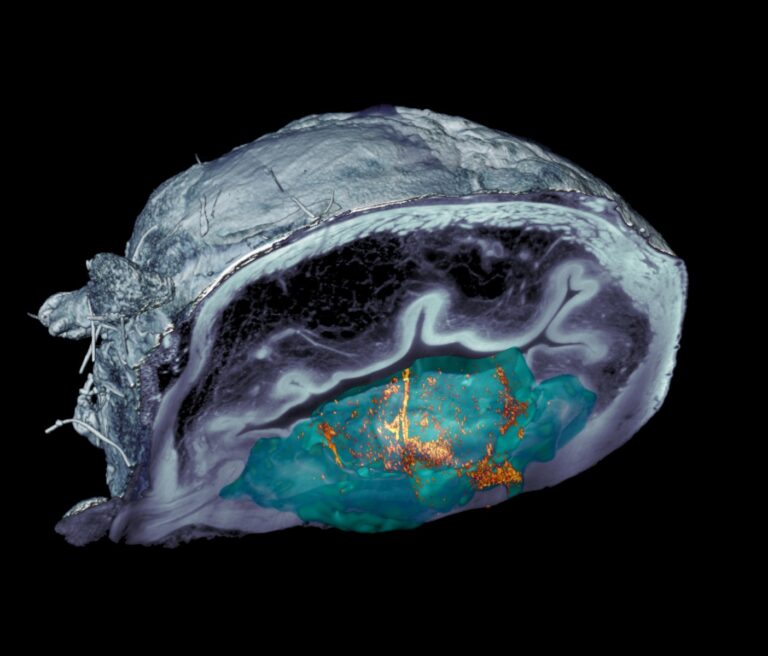

Egy lépéssel közelebb Raymond Kurzweil jóslatainak megvalósulása felé

A jövőkutató a halhatatlanság és a mainál sokkal fejlettebb intelligencia kulcsát a nanorobotokban látja. Egyes kutatók pedig éppen a miniatűr robotok fejlesztésén dolgoznak, kisebb-nagyobb sikerekkel.